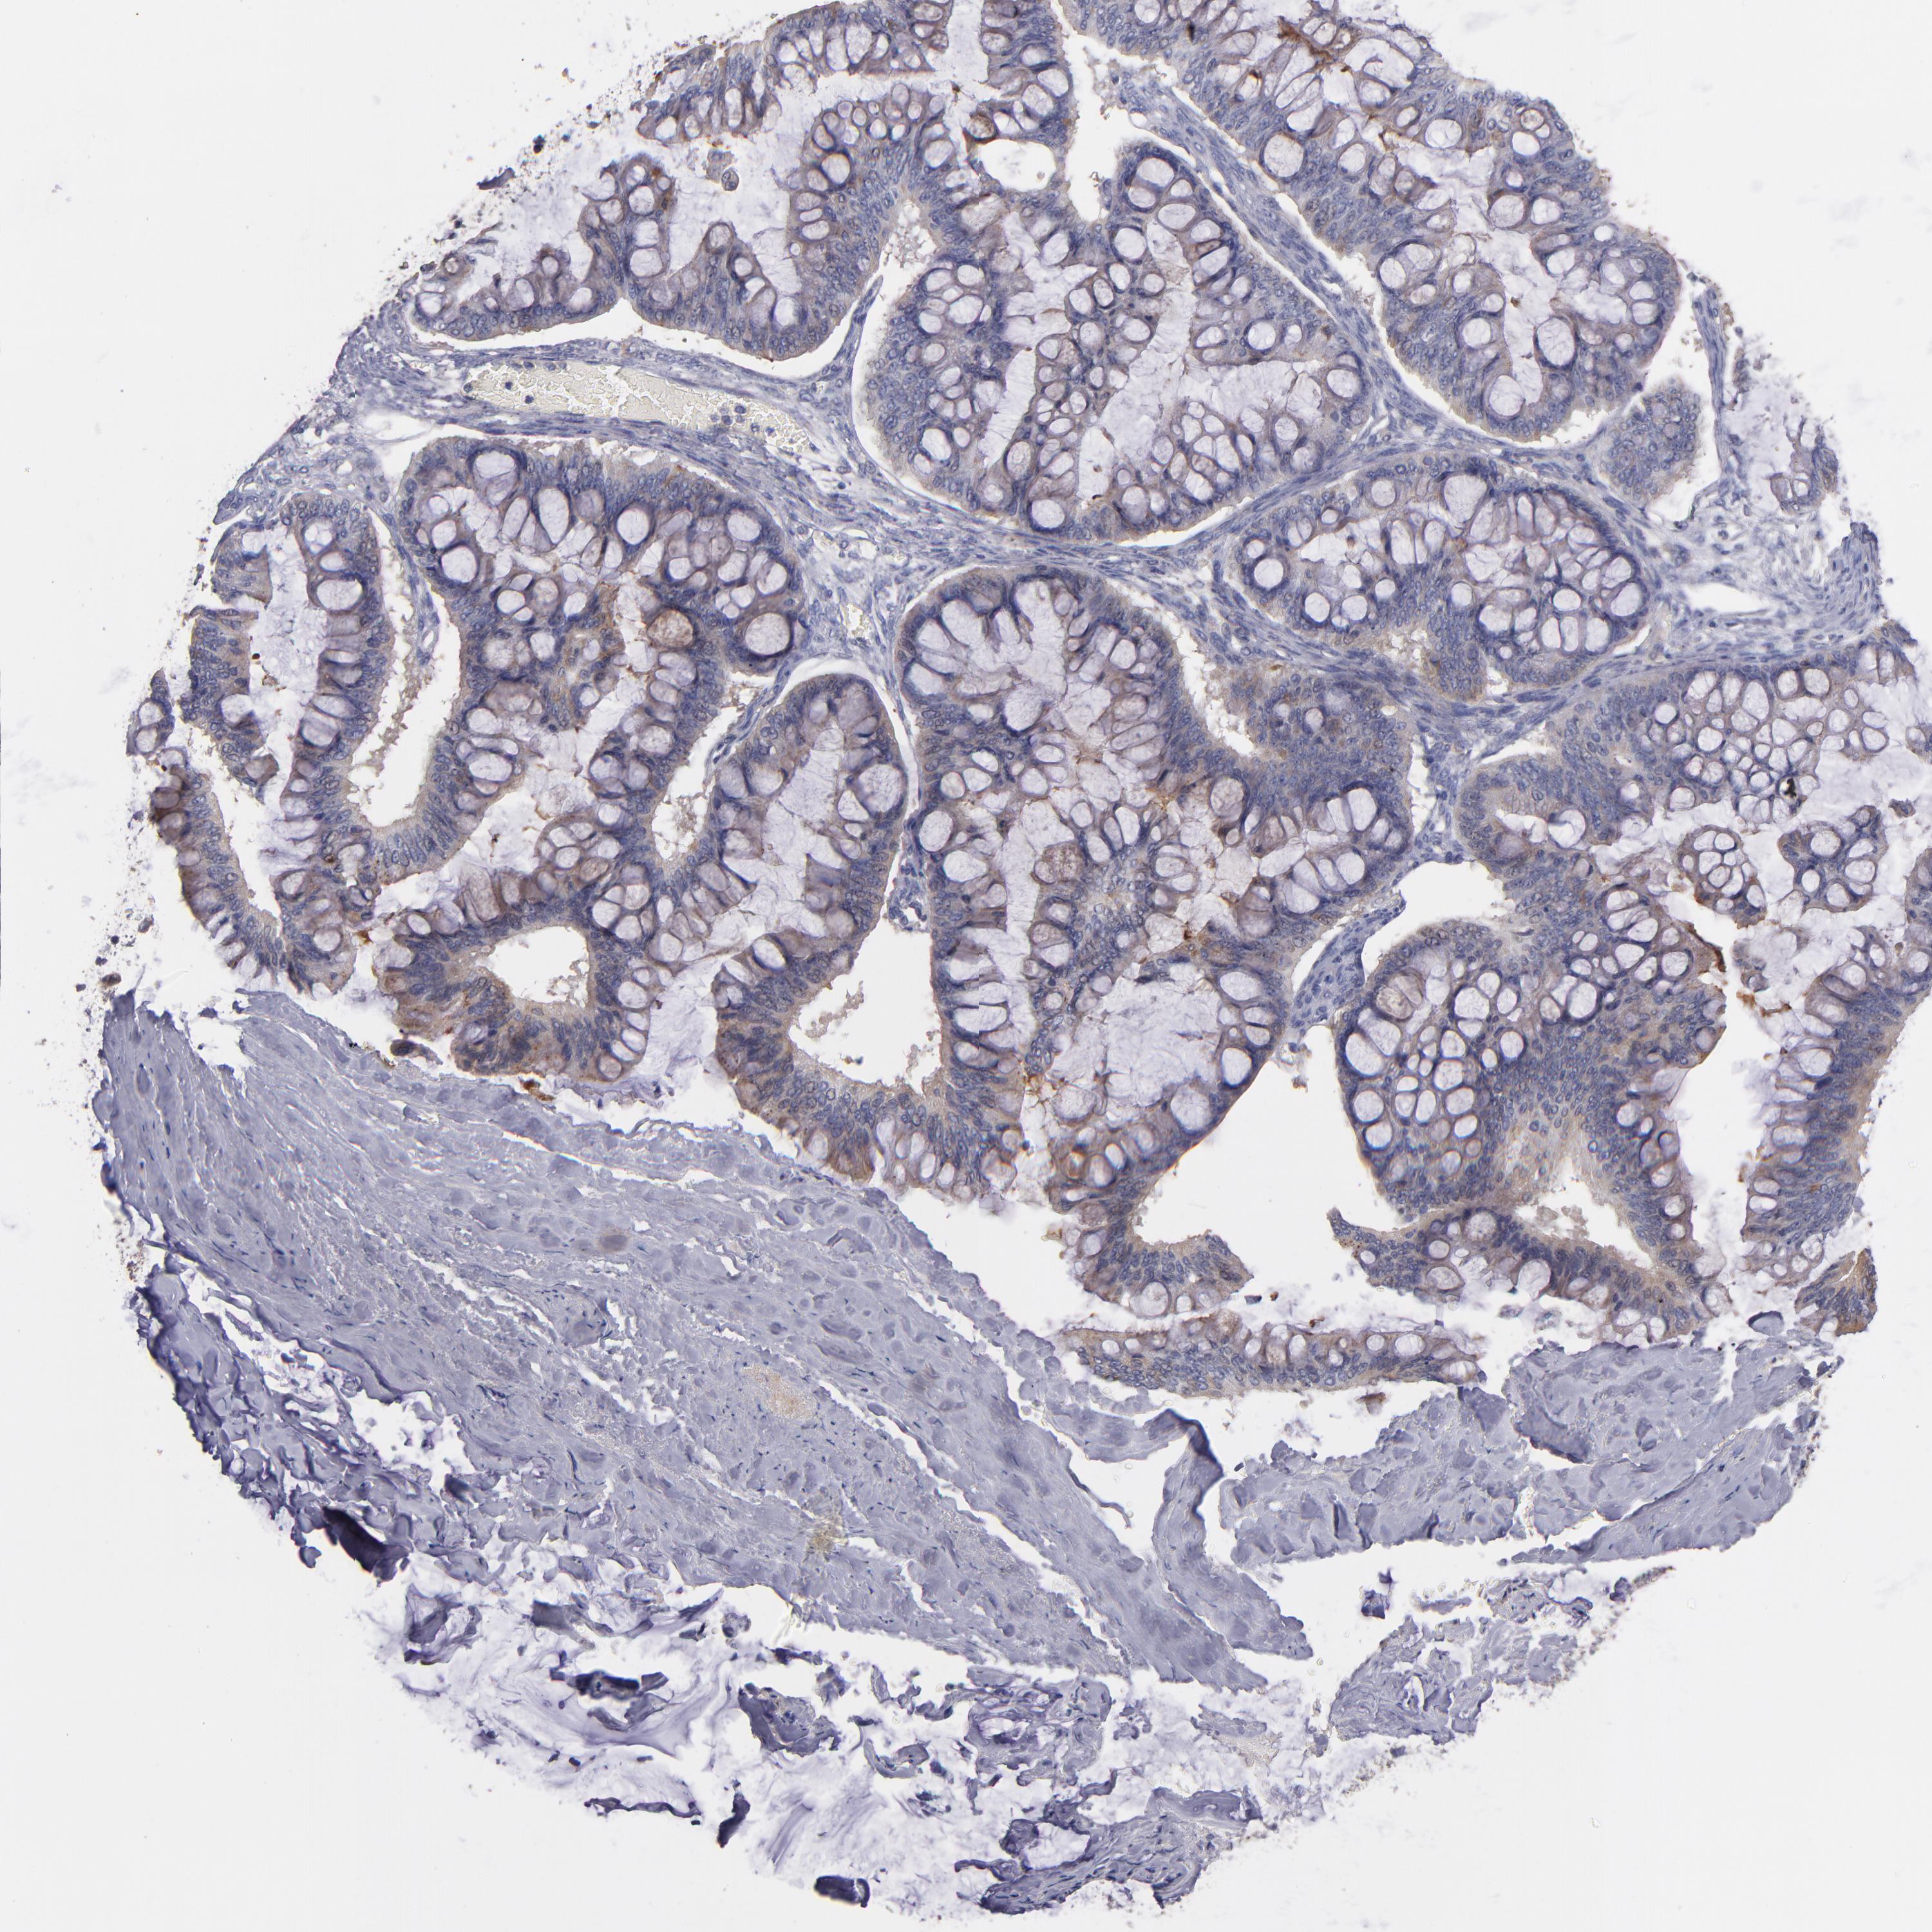

OVARIAN CANCER - Protein expressioni

A mouse-over function shows sample information and annotation data. Click on an image to view it in a full screen mode. Samples can be filtered based on level of antibody staining by selecting one or several of the following categories: high, medium, low and not detected. The assay and annotation is described here.

Note that samples used for immunohistochemistry by the Human Protein Atlas do not correspond to samples in the TCGA dataset.

Antibody stainingi

Antibody staining in the annotated cell types in the current human tissue is reported as not detected, low, medium, or high, based on conventional immunohistochemistry profiling in selected tissues. This score is based on the combination of the staining intensity and fraction of stained cells.

Each image is clickable and will lead to virtual microscopy that enables deeper exploration of all samples and also displays staining intensity scores, fraction scores and subcellular localization as well as patient and tissue information for each sample.

Antibody HPA003047

Staining

High

Medium

Low

Not detected

Intensity

Strong

Moderate

Weak

Negative

Quantity

>75%

75%-25%

<25%

None

Location

Nuclear

Cytoplasmic/membranous

Cytoplasmic/membranous,nuclear

Cystadenocarcinoma, serous, NOS

Cystadenocarcinoma, mucinous, NOS

Carcinoma, endometroid